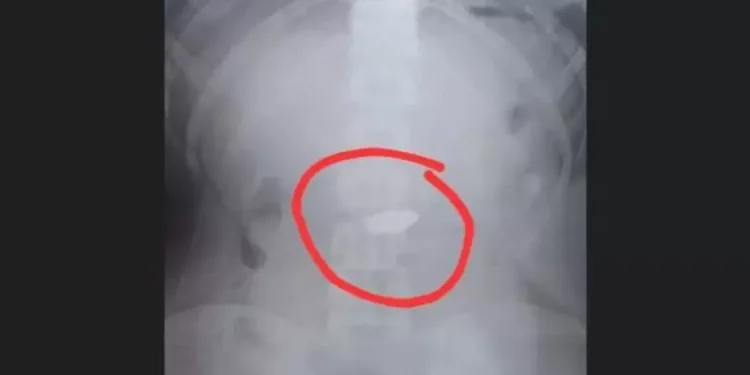

Por volta das 13h o menor foi apreendido no Jardim Virgínia. Apesar do reconhecimento pela vítima, o jovem não portava a corrente roubada. Suspeitando que o adolescente tivesse ingerido o objeto, os guardas o encaminharam à Unidade de Pronto Atendimento (UPA) da Enseada.

No local, após a realização de um exame de raio X, foi confirmado que a corrente estava no estômago do suspeito. Para resolver a situação, o menor foi submetido a procedimentos para induzir a expulsão do objeto, incluindo o uso de laxantes.